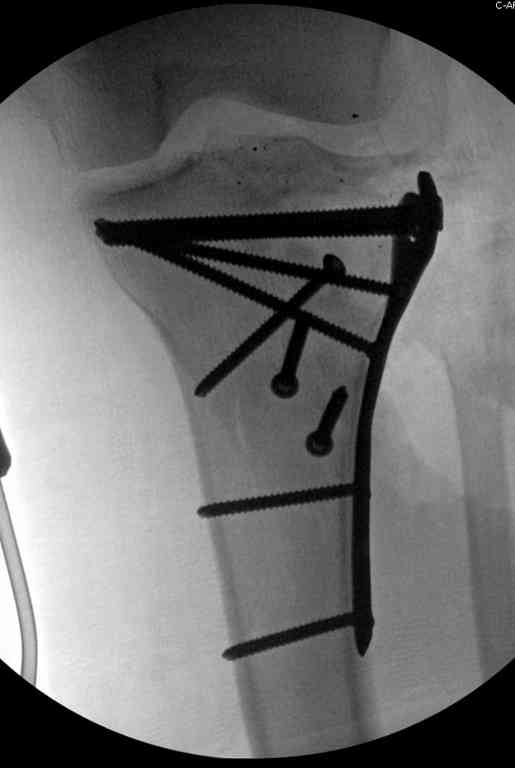

Пожалуйста, снимки.

Коллеги фиксатор Numelock II

На вашем снимке из-за ротации трудно угадать положение пластины, и желательно сделать снимок с захватом верхнего участка бедра.

Одинокий кортикальный шуруп не удержит тибиальный бугор, сустав тибиал плато оставлен без репозиции и фиксации.

Здесь применение материала Plexur http://www.plexur.com для пластики при дефектах кости у больной с огнестрельной раной латерального тибиал плато с повреждением малоберцового нерва. Несмотря на интактный медиальный мышелок, для профилактики от вальгуса установлен АВФ и сделана ангиограмма.

После нескольких обработок и вакуумирования, поэтапно сделана фиксация тибиального бугра шурупами. И окончательную фиксацию закончили латеральной пластиной для тибиал плато и установкой пластического материала.